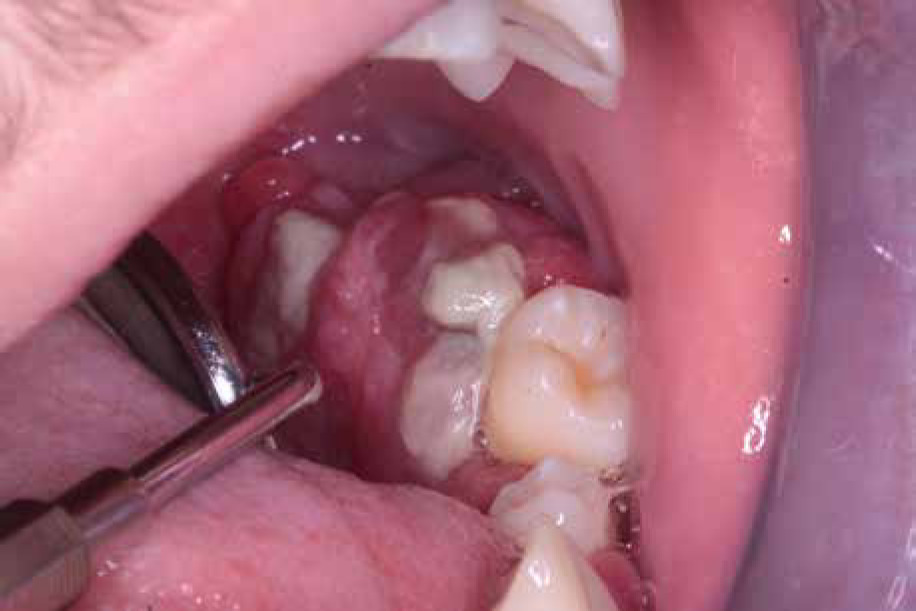

The next year, tartar deposits in the incisors of the mandible and gingivitis were discovered, and the mandibular first molars and central incisors showed signs of second-degree loosening. The patient was recommended to continue conservative treatment and undergo removal of the tartar deposits under antibiotic treatment (amoxicillin with clavulanic acid, 2 doses of 30 mg/kg with an interval of 12 hours, given at home). A few months later (Fig. 5), examination revealed intensified inflammation around tooth 36 with its roots halfway exposed, as well as looseness of teeth 32-42. Extraction of tooth 36 was performed under local anesthesia in an outpatient setting and covered with intravenous antibiotic (amoxicillin with clavulanic acid 30 mg/kg/dose).